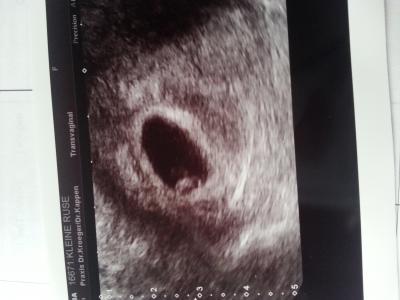

ich bin wieder da vom FA und aus einer leeren Fruchthöhle wurde ein 4,4 mm großer Flips mit schlagendem Herzen.

Bild hänge ich an.